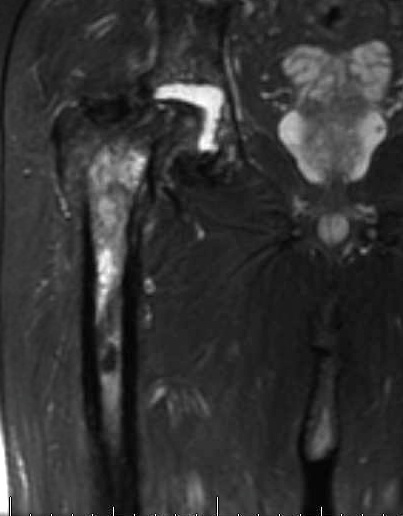

MRI

Increased signal on TI

Abscess

- high signal rim with low signal in middle

- rim / ring enhancement with gadolinium